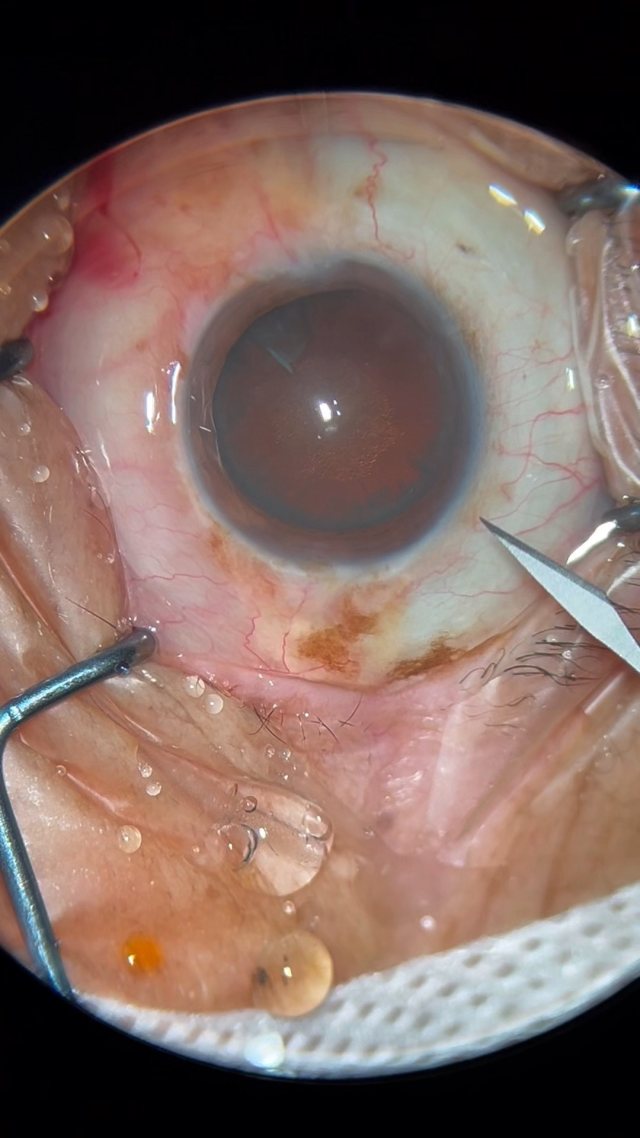

大瓜:湖南省人民医院副院长出轨眼科主任?

护伟达护士

号外号外,湖南省人民医院副院长祖雄兵和眼科主任医师曾琦被指存在不正当关系,并有不雅视频传出。对此,医院工作人员回应:组织正在调查,请给医院宣传部门联系。当地卫生健康委员会对此回应:暂未接到相关的信访反映。祖雄兵为湖南省人民医院副院长,泌尿外科学科带头人。曾琦,博士,主任医师,硕士研究生导师。现任湖南省人民医院眼科副主任、眼科一病区主任,湖南省卫生健康高层次青年骨干人才,湖南省预防医学会眼病防治专业委员会主任委员、湖南省女医师协会眼科专业委员会主任委员、湖南省医学会眼科学专业委员会防盲学组副组长、湖南省医学会眼科学专业委员会眼外伤及职业病学组副组长、湖南省医学会眼科学专业委员会白内障学组副组长、